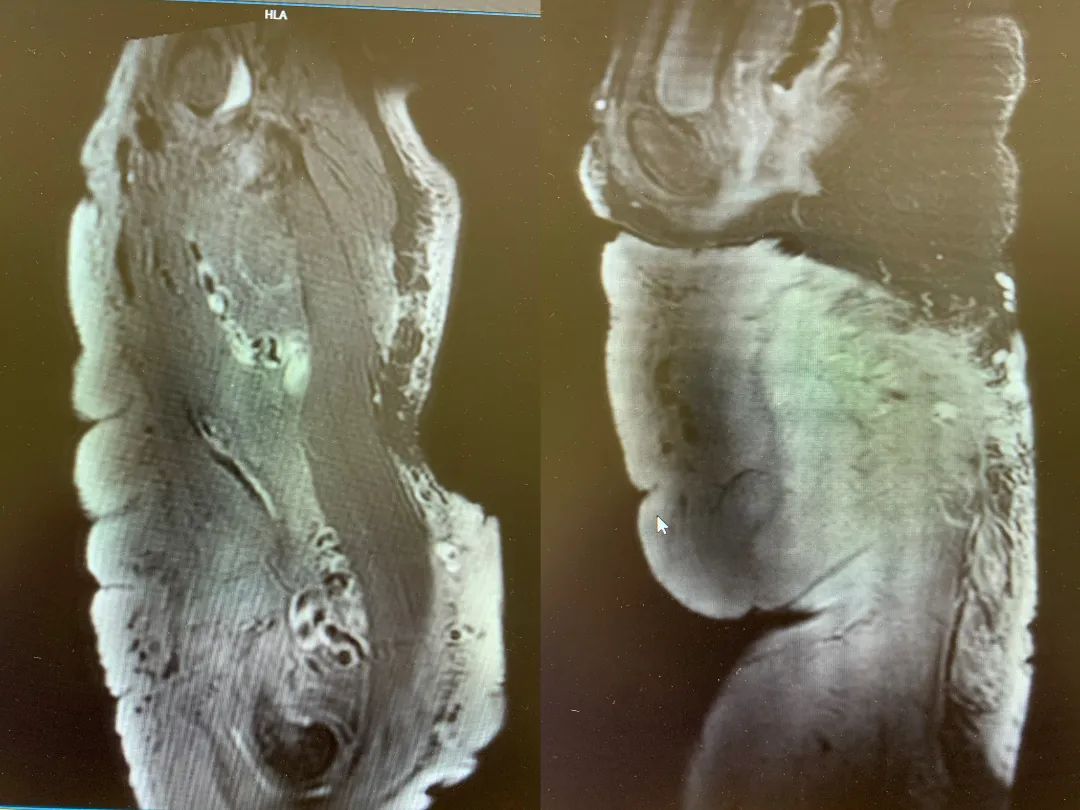

患者陈女士,今年41岁。陈女士介绍说,“从小身上就一直有这个肿瘤,几十年来越长越大,5年前双下肢和背部包块快速变大,此后走路都只能弓着身子,大多数时候都是坐轮椅,非常影响正常生活。”

今年6月份,陈女士来到华西天府医院整形美容科就诊。当第一次会面时,整形美容科陈志兴医生也被患者下半身巨大的肿瘤震惊到了。“之前临床也有遇到过不少神经纤维瘤患者,但这么大体积的确实很少见。”陈志兴医生说。

陈志兴医生表示,患者因为肿瘤巨大,导致身体变形、脊柱侧凸而无法正常行走,且在切除如此巨大的手术时出血风险高,手术难度非常高。

由于瘤体组织脆弱,血窦和血管异常丰富复杂,其颜色质地类似于富含血管的“魔芋”,甚至一夹就烂,术中止血极其困难,往往容易引发大出血,严重威胁患者生命。

针对小型体表肿瘤,理想条件下应一次手术予以全部切除。而陈女士瘤体过大,双下肢均有巨大瘤体,瘤体内含血量巨大,若一次切除出血量过大,手术时间长,风险成倍增加,术后恢复更困难。考虑到患者身体承受能力,经过详细商讨,陈志兴医生决定分次手术:第一次先从患者左腿较小瘤体入手切除,待身体恢复后,再进行第二次手术切除右腿瘤体。

经过不断的努力,岑瑛、陈志兴医疗小组和袁丁团队成功完成手术,共切除瘤体重达约10公斤,患者术中出血约1500-2000ml(相当于正常人1/3-1/2的血液),输血2400ml。